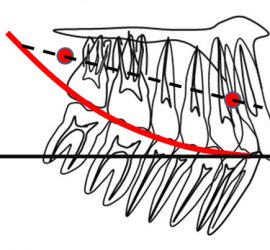

Аппарат представляет собой проволочный нёбный бюгель, который используется для стабилизации положения моляров, после лечения дистализирующими аппаратами, а так же для предотвращения потери места при лечении с удалением зубов. Жёсткая фиксация кнопки Нансе с кольцами создает прочную конструкцию для удержания достигнутого результата лечения.